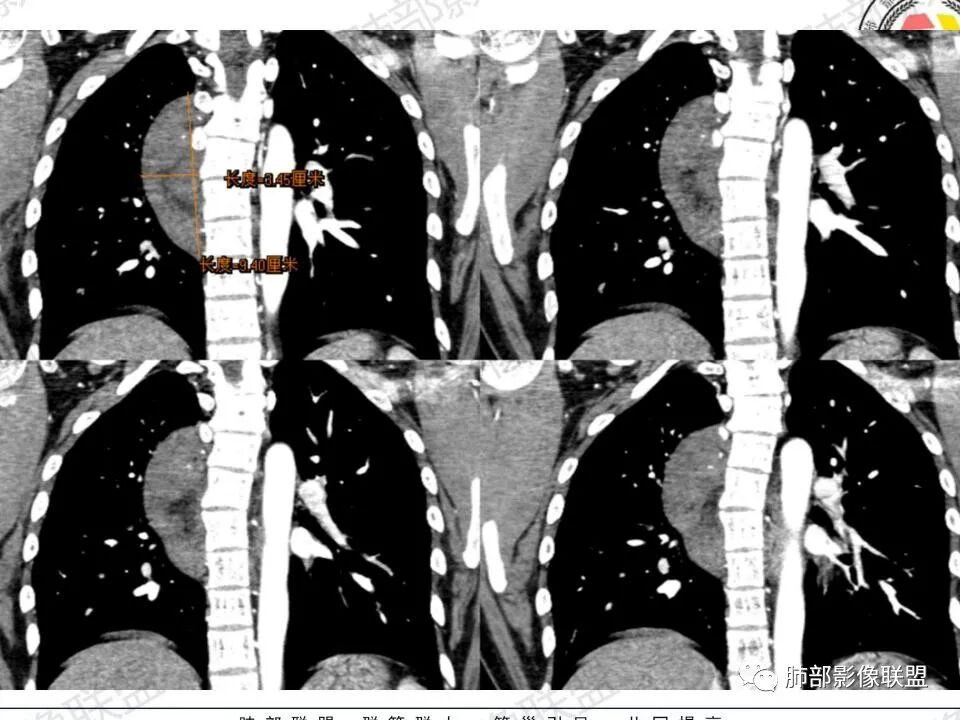

2.右后纵隔脊柱旁上下方向贴伏块影,“肾”形外观,边界清晰,密度不均,中央区域见脂肪密度影引向椎体前方,未见液性密度管腔影及钙化。

1.肿块未横向经椎间孔延入椎管,或形成所谓“哑铃状”外观等,没有显示出沿脊神经根生长特征。长轴顺脊柱贴行恰好与交感神经路径相一致。

瘤体体积常较大,大部分有完整包膜,边界清楚,可沿周围组织间隙嵌入性生长,由于肿瘤质地较软,使得肿瘤可呈多种形态,其易沿着周围组织间隙生长、包饶,但不挤压周围器官或组织,邻近血管被包绕或穿行,呈嵌入式或铸型生长方式,这是后纵隔神经节细胞瘤的特征性表现;

还有另外一种形态学特征,瘤体的上下径线常大于其他径线,这可能是神经节细胞瘤起源于交感神经节,而交感神经节纵向分布于近脊柱中线两旁及前方,导致了后纵隔神经节细胞瘤纵向生长的范围大于向其他方向生长的范围,其上下可跨越多个椎体。但后纵隔神经节细胞瘤体积较小时,则常呈圆形、椭圆形、哑铃形等形态,紧贴后纵隔或后胸壁。

(神经源性肿瘤的解剖位置很重要,因为它是沿着神经干方向走形,所以病灶的长轴是跟沿神经干方向的;后纵隔内神经鞘瘤最常见的是脊神经刚出椎间孔位置,并沿着肋间神经分布(水平分布),所以后纵隔神经鞘瘤明显横径大,上下径小;神经节细胞瘤沿着椎旁上下方向分布(上图黄色梭形形状为神经节),所以表现为上下径长。)